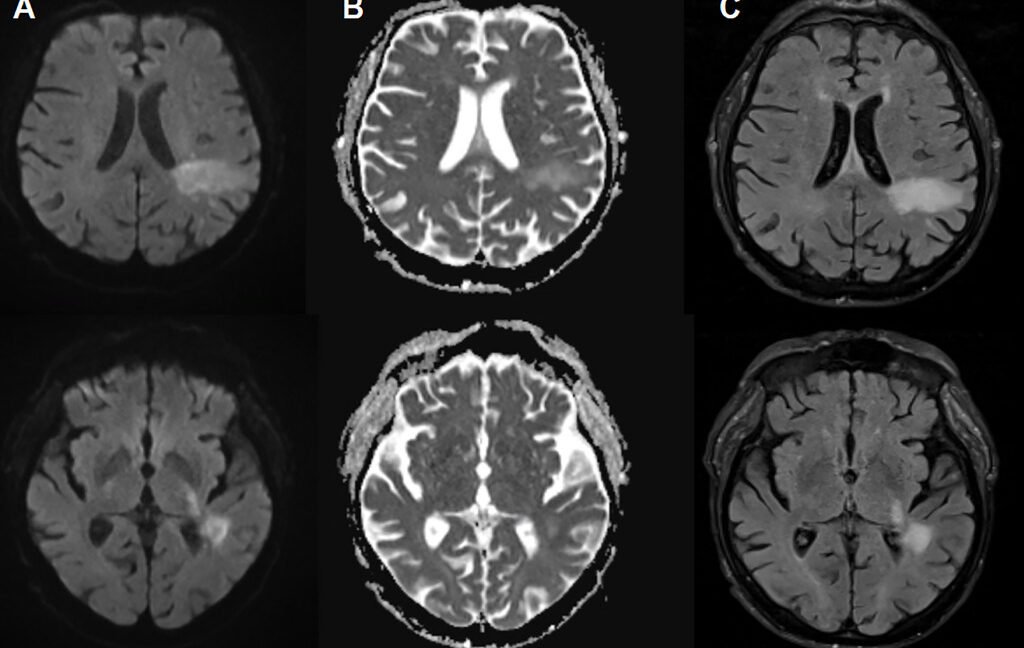

In PML, the new disease-causing virus or “PML-type” JC virus actively invades the brain, blowing up specific brain cells, including the cells that form the insulating myelin sheaths that protect nerve cells. This leads to extensive demyelination, which results in nerve cell dysfunction and death. On imaging, PML can show up as signature lesions in the brain. Those imaged lesions, paired with test findings of JC virus DNA in cerebrospinal fluid, are how PML is diagnosed. But for patients experiencing PML, the symptoms can mimic everything from a stroke to multiple sclerosis, causing problems like speech impairments, visual defects, motor dysfunction, and seizures.